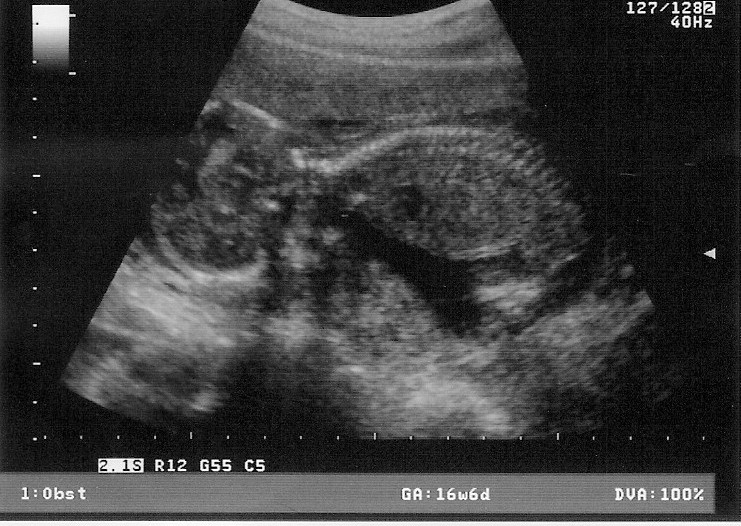

Confirmed this morning, by ultrasound. It’s a boy. Which means, because the wife just has to have a little girl, who according to her will have “big boobs and long hair and be absolutely gorgeous”, a cute little creature that she can spend hours and hours and hours dressing and playing with, an addition that I would have to build a new closet for, I have to go through this damn pregnancy shit yet again. More early morning nausea. The totally irrational mood changes. The “oh, you carry this because I’m pregnant” shit. The even worse “Oh you change his diaper because I’m pregnant” shit. And, the unintended weight gain, not her, but me. God knows I have to eat out of sympathy when she gorges. Which is almost on an hourly basis. But, there are advantages to having another little guy in the family; more to play Left 4 Dead with on the computers, and, savings of unknown amounts of hundreds of dollars when the wife can’t buy baby Louis Vuitton purses. Yes, they make those for little girls….

Little guy, code named “Boris 2”, is due May 10, or somewhere thereabouts. Not sure what to name him, but, oh, we’re thinking about, um, “Richard”. Easy to remember, just like the other little guy, and yes, me. By the time I’m done, I’m going to put George Foreman to shame...